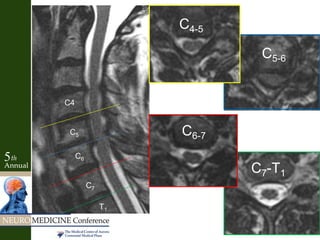

C5-6

C5C6

C6

C5

C6 C5

C6-7

C7

Case Example • 45yomale with neck pain radiating into right arm, right deltoid/bicep weakness, and numbness in right thumb and index finger • No reflex abnormality • + Spurling’s test to the right

Key Factors • Neckpain and radiculopathy • Weakness in muscles supplied by same spinal nerve root (C6), but different peripheral nerve branches (deltoid- axillary n., bicep- musculocutaneous n.) • Sensory disturbance concordant with C6 • Reflexes normal • Positive Spurling’s test • Concordant MRI

Case Example • 64yo female with diffuse neck pain – Radiates bilateral arms • No weakness or numbness • Slightly hyperactive reflexes • Negative Spurling’s

Key Factors • Neckpain and “radiculopathy” into arms • Interscapular pain – Cloward 1959- Disc herniations of lower cervical levels induced spasms of para-scapular muscles • Motor/sensory exam not localizing • Myelopathic with hyperactive reflexes • Negative Spurling’s • Positive discogram – Reproduced pain at levels and no pain at adjacent levels • Concordant MRI